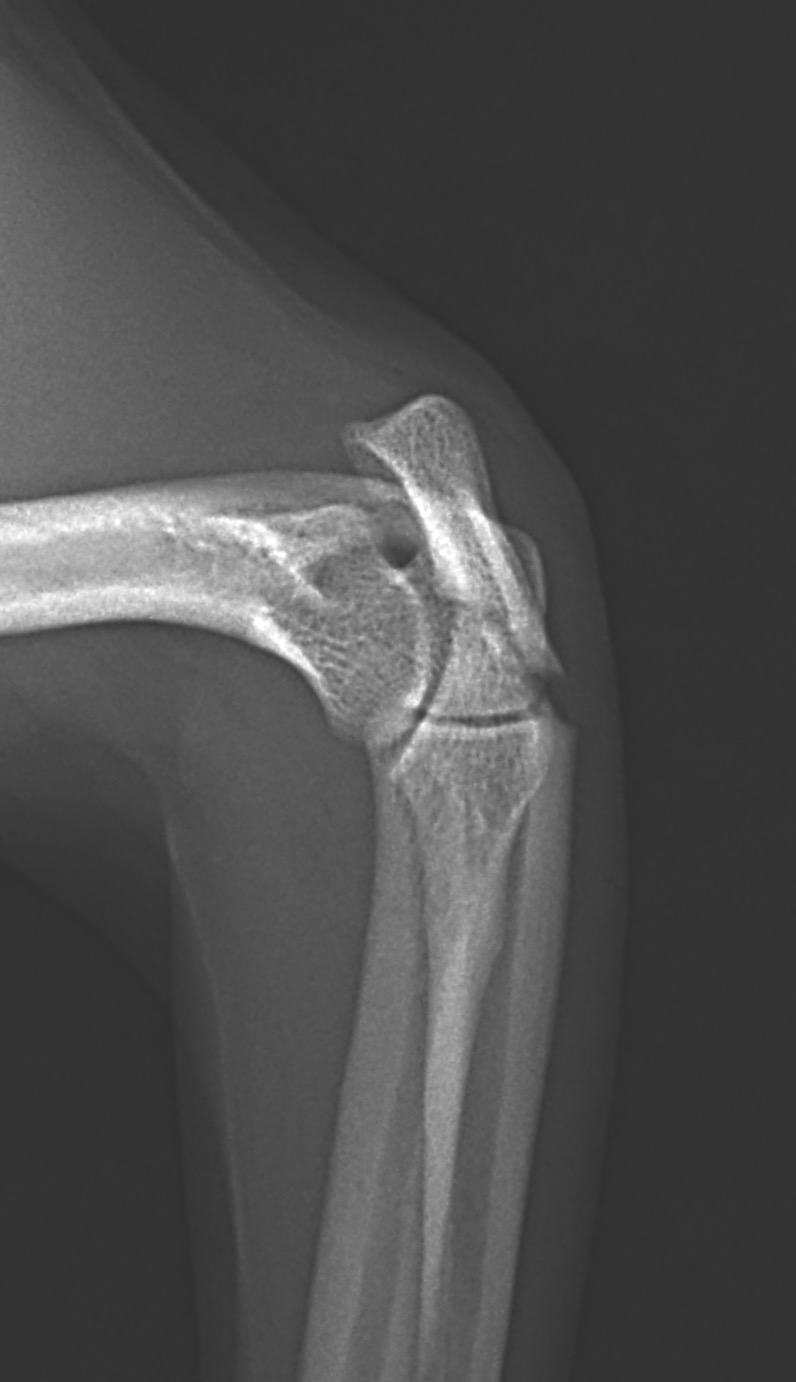

尺骨近位端肘頭骨折

尺骨の近位端の肘頭骨折をしているワンコがいるので手術で対応して欲しいと連絡がありました。高いところからジャンプして着地に失敗してしまったとの事です。さて、この部分の骨折は上腕三頭筋の牽引力に抵抗するための強固な固定が必要です。橈骨遠位端用の1.5 mm Titanium T-typeLocking Plateで接合術を行います。手術をする事で、早々に肘の曲げ伸ばし運動などのリハビリテーションを実施する事が可能となり、後遺症の発生を少なくする事を目的としています。